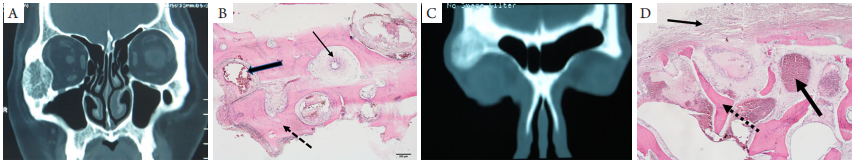

图2 骨内血管瘤CT图像和病理学表现

(A)例1患者CT图像:右侧颧骨膨胀性生长肿物影,呈栅栏状、蜂窝状混杂密度影,内密度不均,可见粗大骨嵴影;(B)例1患者病理结果,骨小梁(虚线箭头)间可见管腔大小不等的血管结构(粗、细箭头);(C)例2患者CT图像:右侧眶骨肿物,内高低密度混杂;(D)例2患者病理:细箭头指向骨膜,虚线箭头指向骨样基质,粗箭头指向位于骨小梁间的海绵状血管瘤结构(HE,×5)。

骨内血管瘤是一种骨内血管畸形,部分患者伴有局部外伤史;肿瘤分为海绵状血管瘤、毛细血管瘤和混合型3种类型[4]。海绵状血管瘤主要由扩大的血性窦腔构成,毛细血管瘤为增生扩张的毛细血管构成。肿瘤位于骨小梁之间,因此在CT上主要表现为密度较低的肿物间有放射状高密度的骨小梁结构,呈现出典型的“栅栏状”“蜂窝状”[5]。偶也可表现为囊状结构,可能是当肿瘤较大时压迫骨小梁导致其破坏和吸收而形成。在本组病例中,病例1的CT表现密度较低,有典型的“栅栏状”状结构,术中出血较多,术后病理结果显示肿瘤中有管腔大小不等的血管样结构;病例2的CT显示为不均匀的较高密度影,术中出血较少,术后病理示血管组织主要为薄壁血管或血窦。因此,我们可以通过影像表现对组织成分有一定的了解,对于在CT上表现为密度较低且有典型的“栅栏状”结构的一类肿瘤,可能血管成分含量相对较多,因此术中较易出血;而对于密度较高的一类肿瘤,组成的血管成分主要为血窦,术中不易出血。